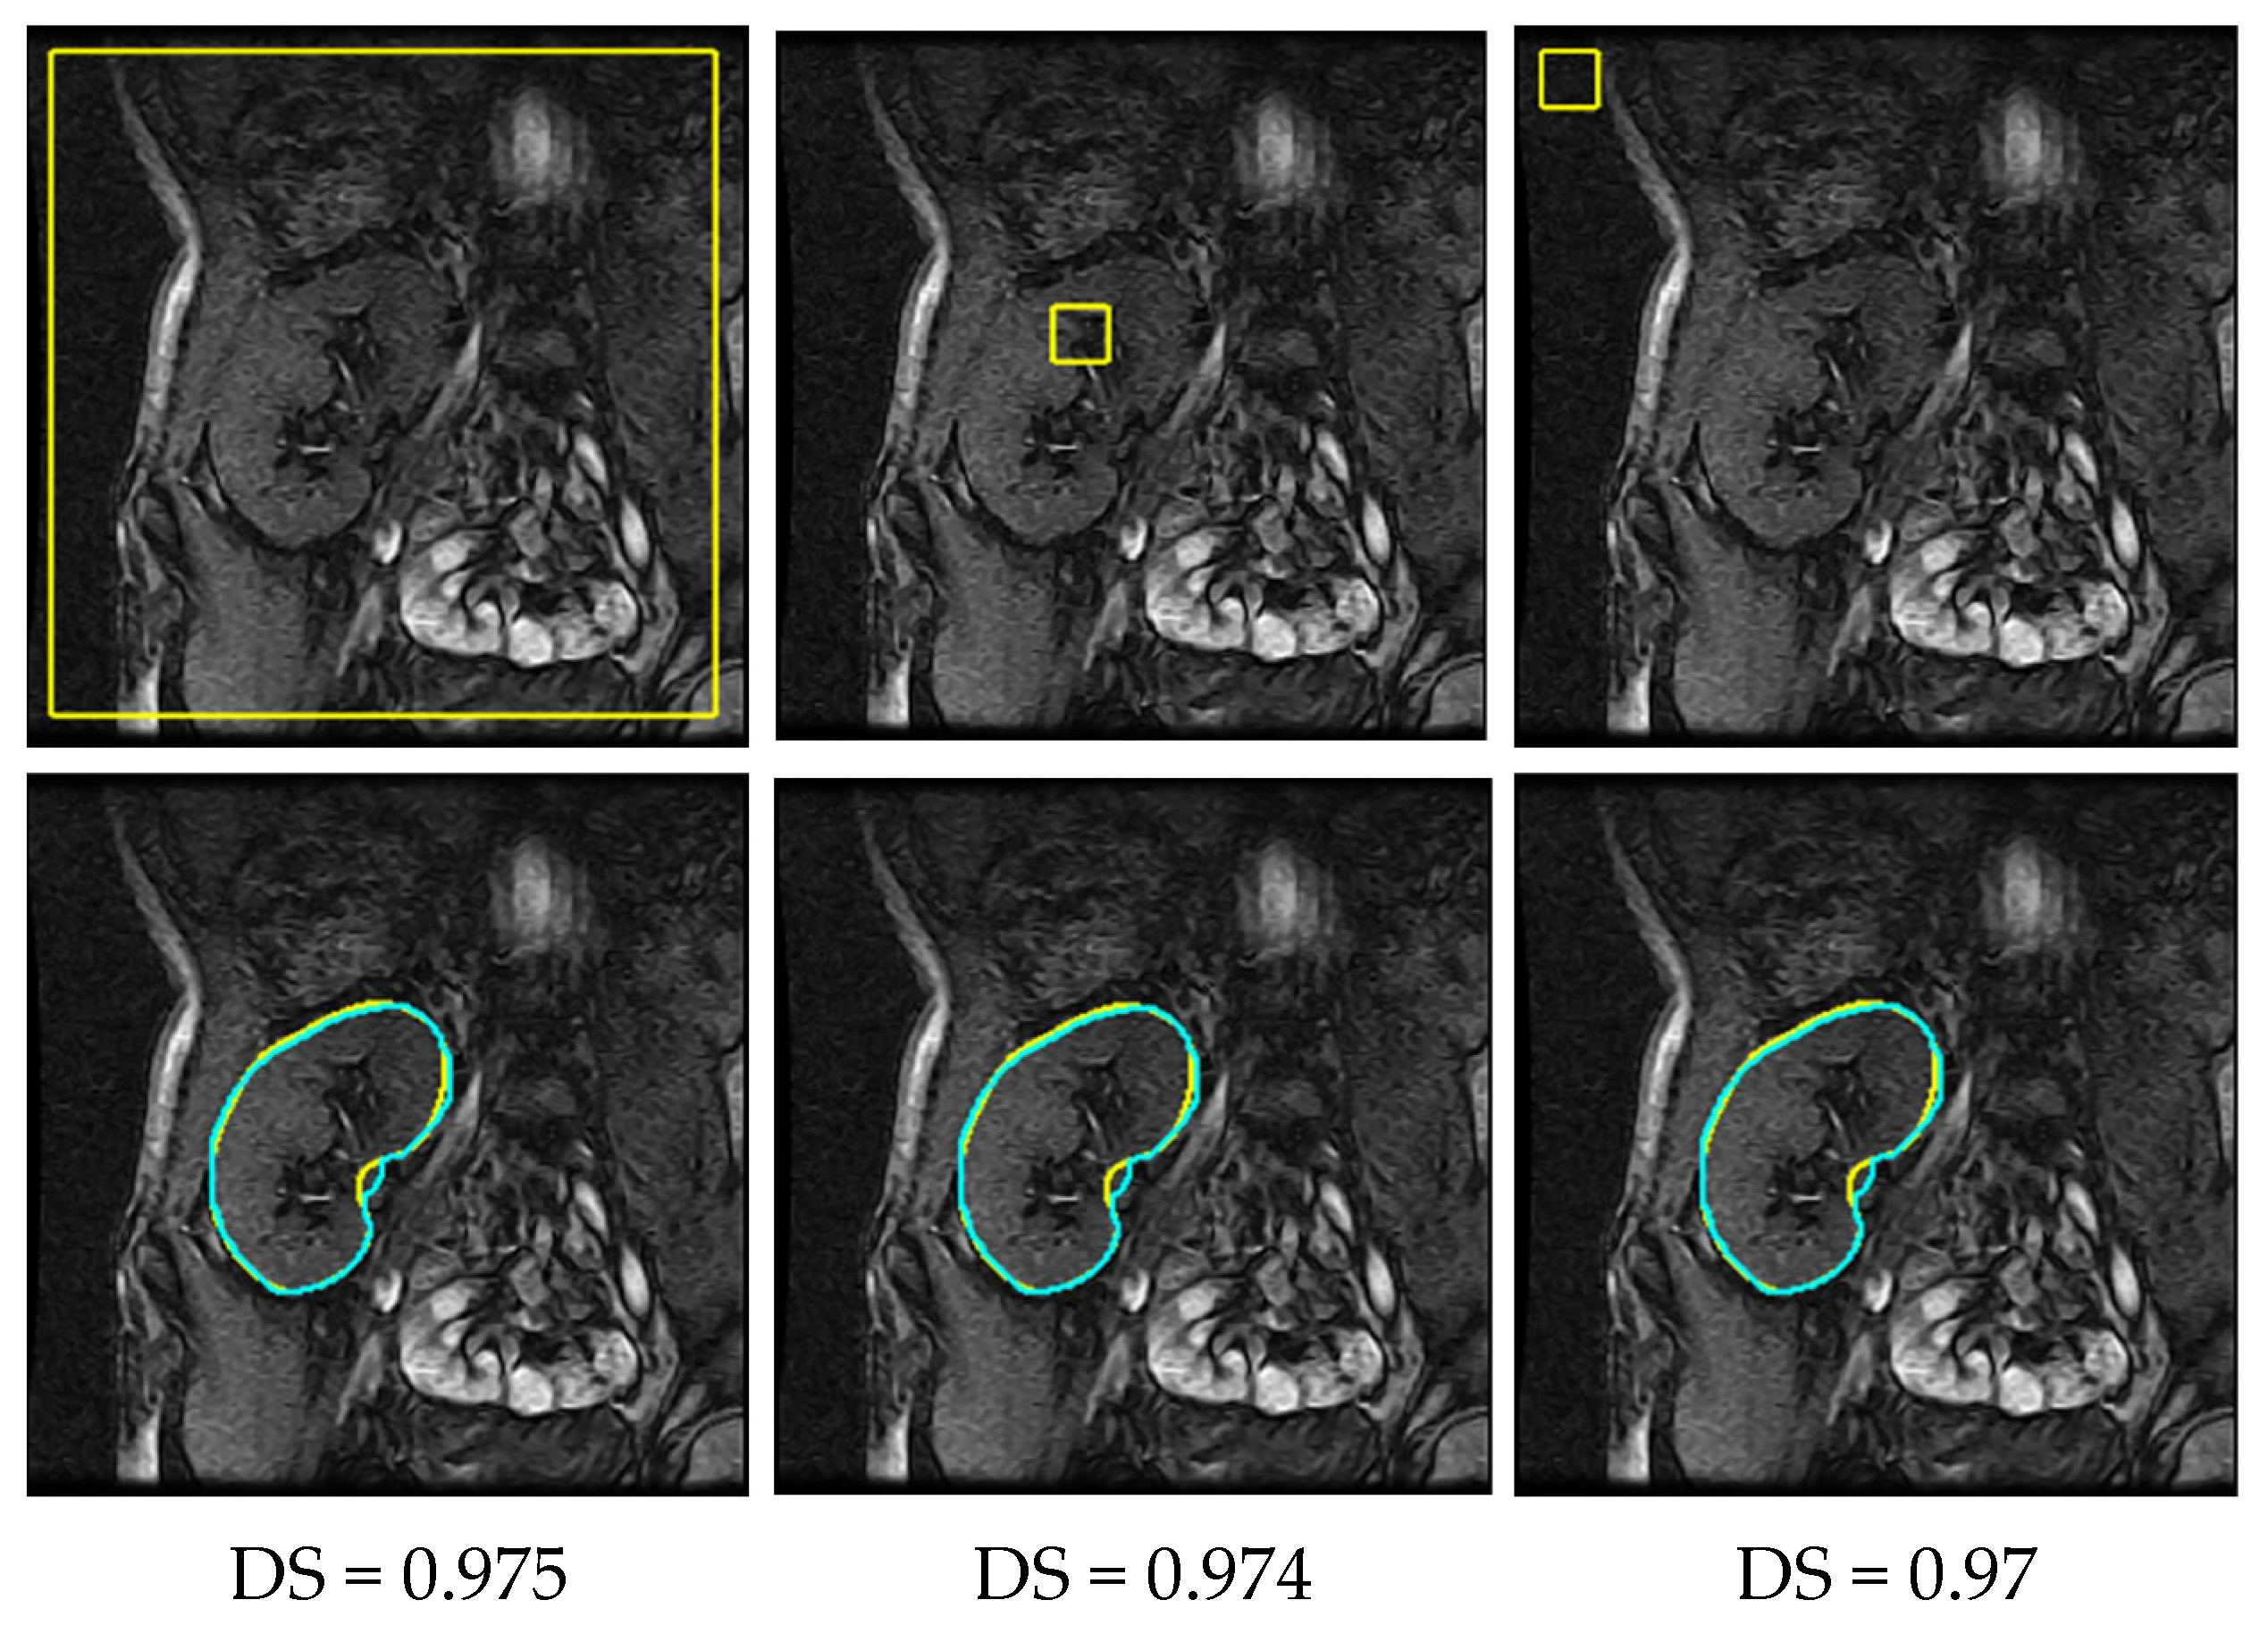

2.1. Data

3.2. Performance Evaluation

4.2. Results